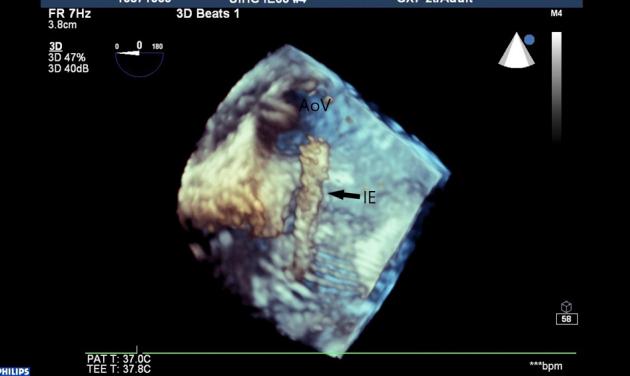

Echocardiographic Findings in Children with Native Mitral Valve Masses Complicated by Systemic Embolization.

• Case of mitral valve IMT with embolization. • Case of mitral valve endocarditis with embolization. • Use of 2D and 3D echocardiography for management of mitral valve masses.

• 二尖瓣内膜中层厚度增加伴栓塞病例。• 二尖瓣心内膜炎伴栓塞病例。• 二维和三维超声心动图在二尖瓣肿物管理中的应用。